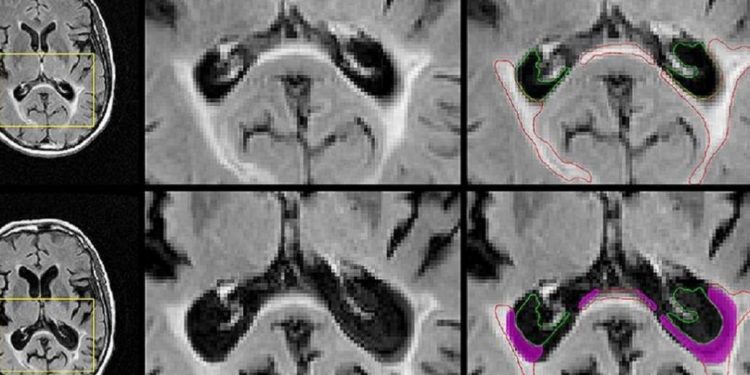

Желтые прямоугольники показывают область, увеличенную слева.

Верхний ряд показывает базовые изображения;

внизу, последующие изображения.

Пурпурный указывает области, которые были повреждены в начале, которые растворились в спинномозговой жидкости в последующем.

(Фото любезно предоставлено UB Jacobs School of Medicine и Медико-биологические науки)